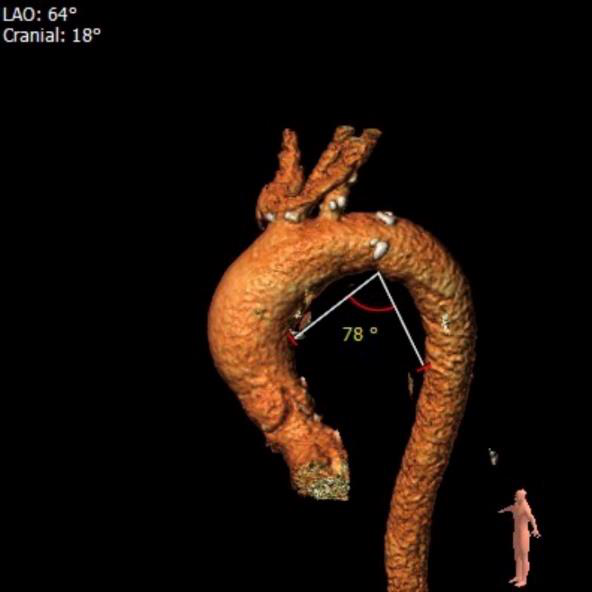

①瓦氏窦整体形态偏大,且伴有主动脉瓣中度关闭不全。

②无冠瓣瓣叶钙化程度较重,结合瓣上结构的特点,较大可能影响瓣膜植入后的形态及贴壁性,瓣周漏发生的风险偏高。

主动脉根部造影提示瓦氏窦整体形态较大,无冠瓣瓣叶钙化斑块程度较重。

瓣膜展开后与术前策略讨论的风险预期相符,受无冠瓣较重钙化和瓣上结构整体的影响,瓣膜释放后的腰部形态受限,决定使用25mm球囊后扩治疗。

最终瓣膜形态和位置良好,造影无明显瓣周漏和返流。